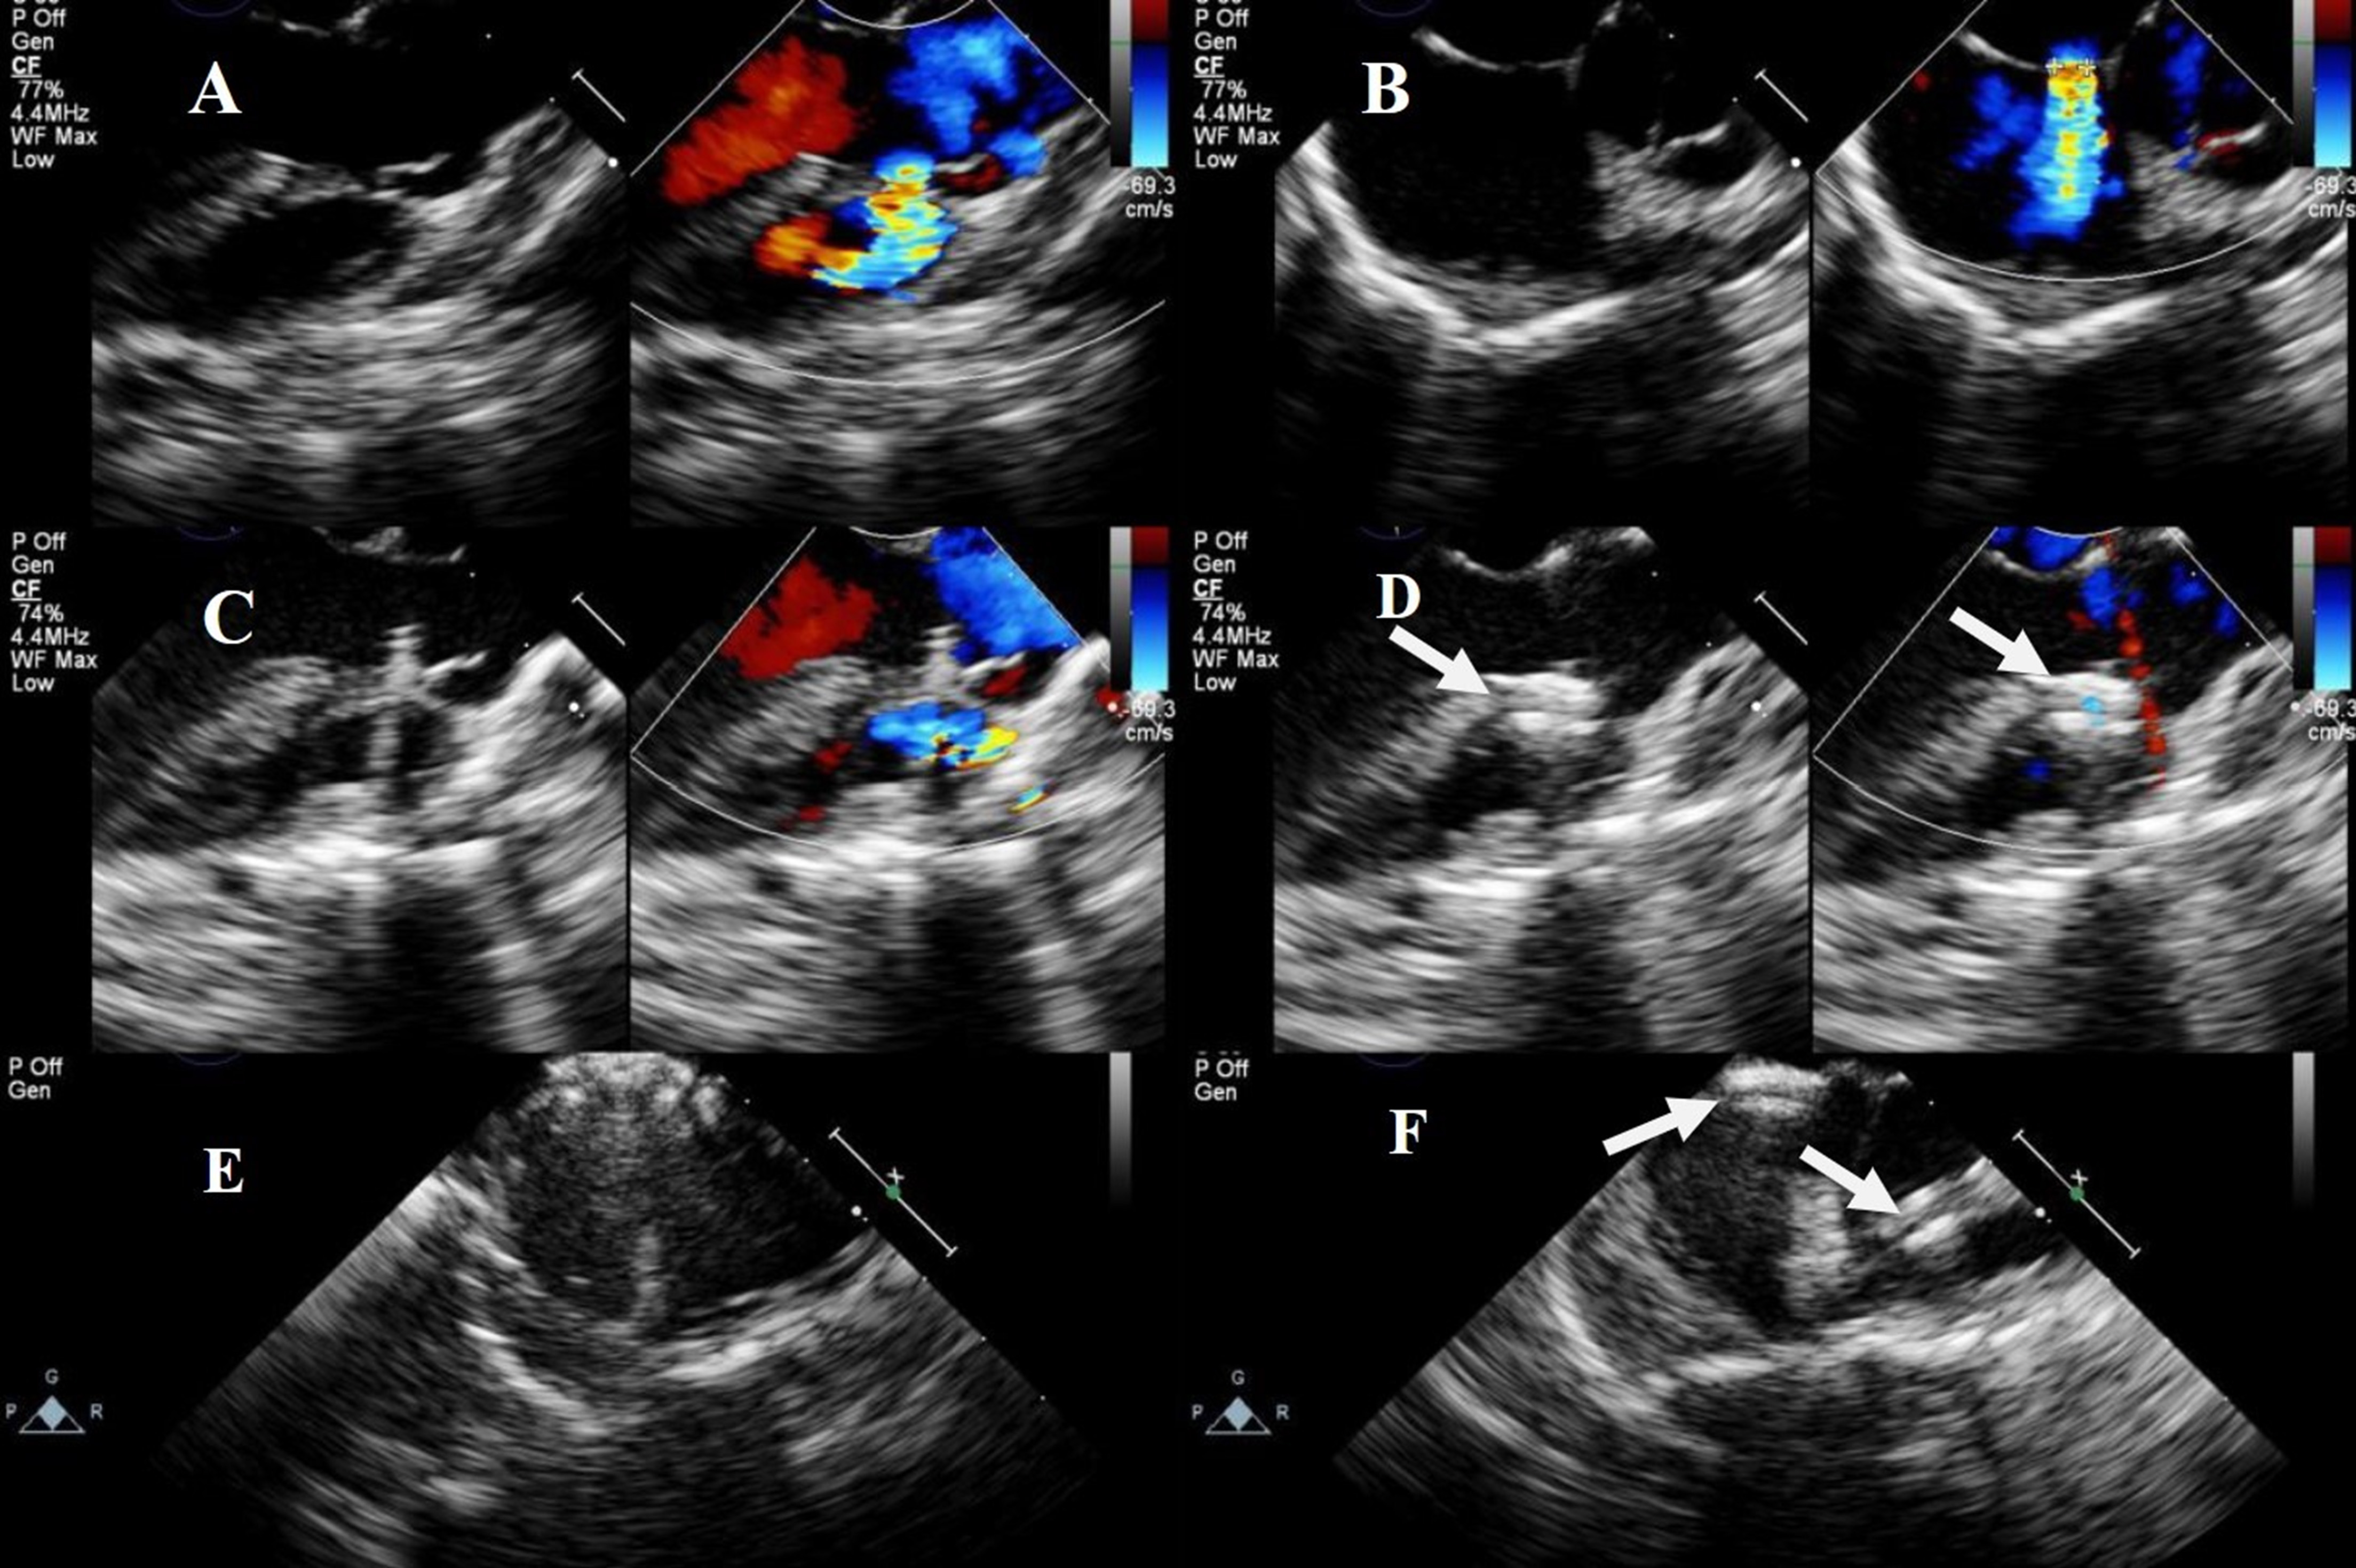

Eleven patients (five males and six females) underwent percardiac combined with percutaneous approaches closure. Among these patients, three had DCVSD, one had apical multiple muscular ventricular septal defects (mVSDs) (with three holes), and six had PmVSD (with an AV distance of 0 mm), including one with a double-hole PmVSD. All patients had an ASD. The median age was 3.8 years (2.5 years to 29 years), and a median weight of 19 kg (13 kg to 73.3 kg). The VSD entry diameter was 7.70

Two occluders were used during surgery on one patient with apical multiple mVSDs (three holes): a 6 mm waist-diameter muscular occluder was used to close the “middle hole”; meanwhile, the “lower hole” was closed by squeezing the occluder on the atrial septum. However, due to the wide defect spacing and TEE showing a significant shunt in the “upper hole”, a 5 mm waist-diameter muscular occluder was subsequently used to close the “upper hole” (Fig. 6).

Fig. 6. Transesophageal echocardiography and X-ray images of the combined lower mini-sternotomy perventricular approach for treating multiple mVSDs combined with a percutaneous approach for treating ASD. (A) Delivery sheath passing through apical mVSD. (B) Successful occlusion of multiple apical mVSDs using two VSD occluders. (C) Postoperative chest frontal view showing two VSD occluders and one ASD occluder. (D) The chest lateral view shows two VSD occluders and one ASD occluder. Note: arrow = occluder.